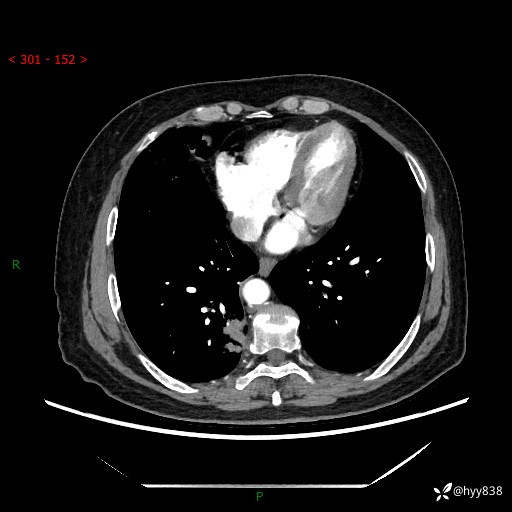

增强动脉期+静脉期

两期CT值:55Hu 53hu